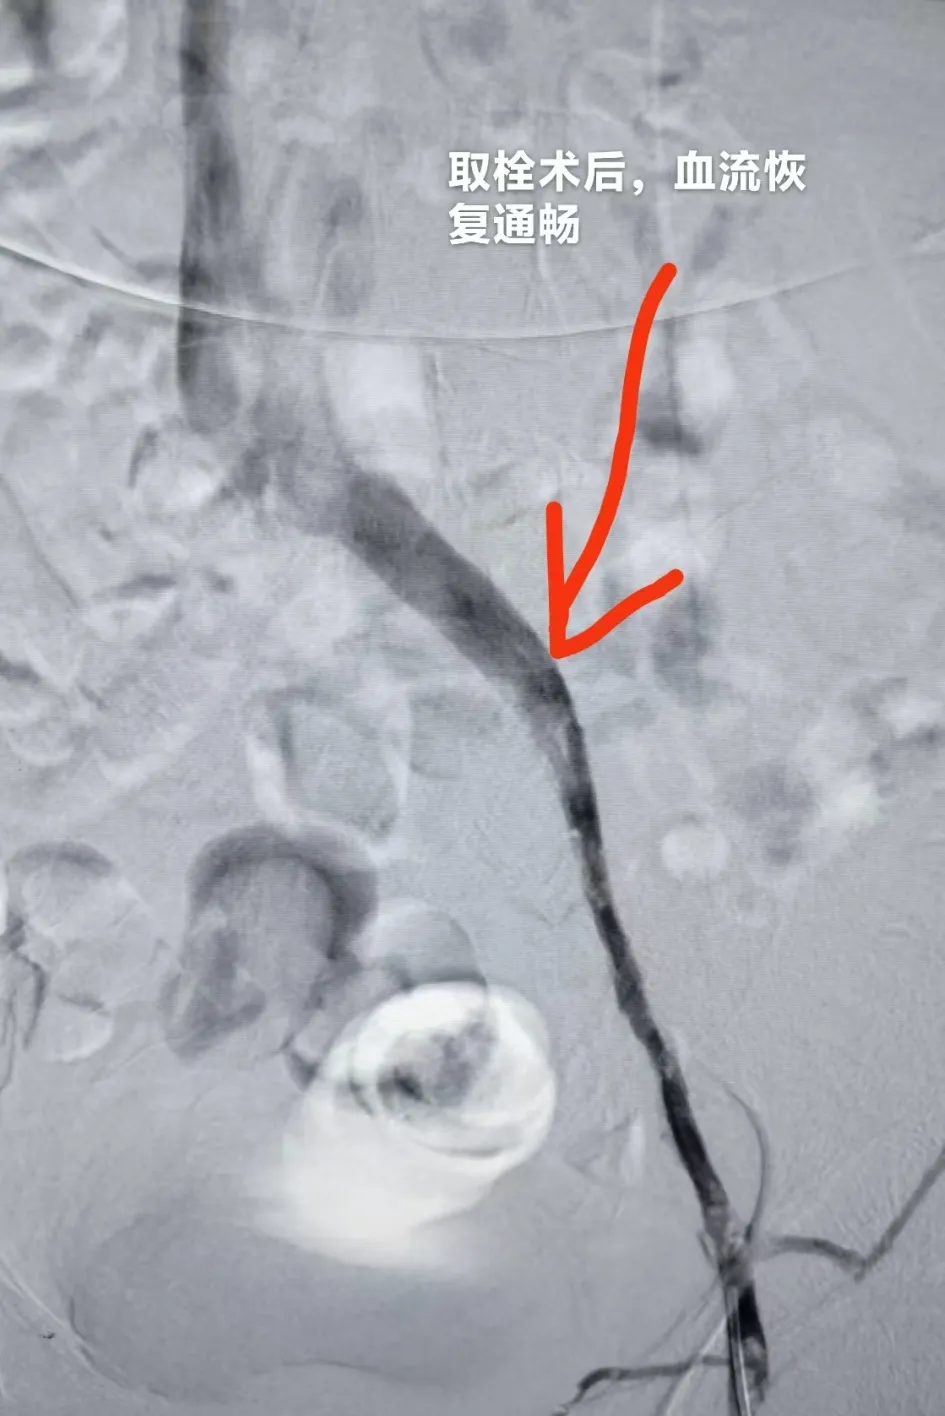

手术当天,王建国副院长在局部麻醉下精准操作:穿刺、置管、造影一气呵成,屏幕上清晰显示——李先生左髂静脉因压迫变窄,血栓堵塞范围从髂静脉延伸至下肢深静脉,病变血管狭窄超过80%,血流几乎中断。团队先注入溶栓药物,15分钟后,借助专用抽栓导管缓慢抽吸,大量棕褐色的混合性血栓被成功吸出,体积约50ml;随后逐级使用不同规格的球囊,对狭窄的股腘静脉、髂静脉反复扩张,直到造影显示:原本堵塞的静脉通畅度显著提升,血流顺利回流。